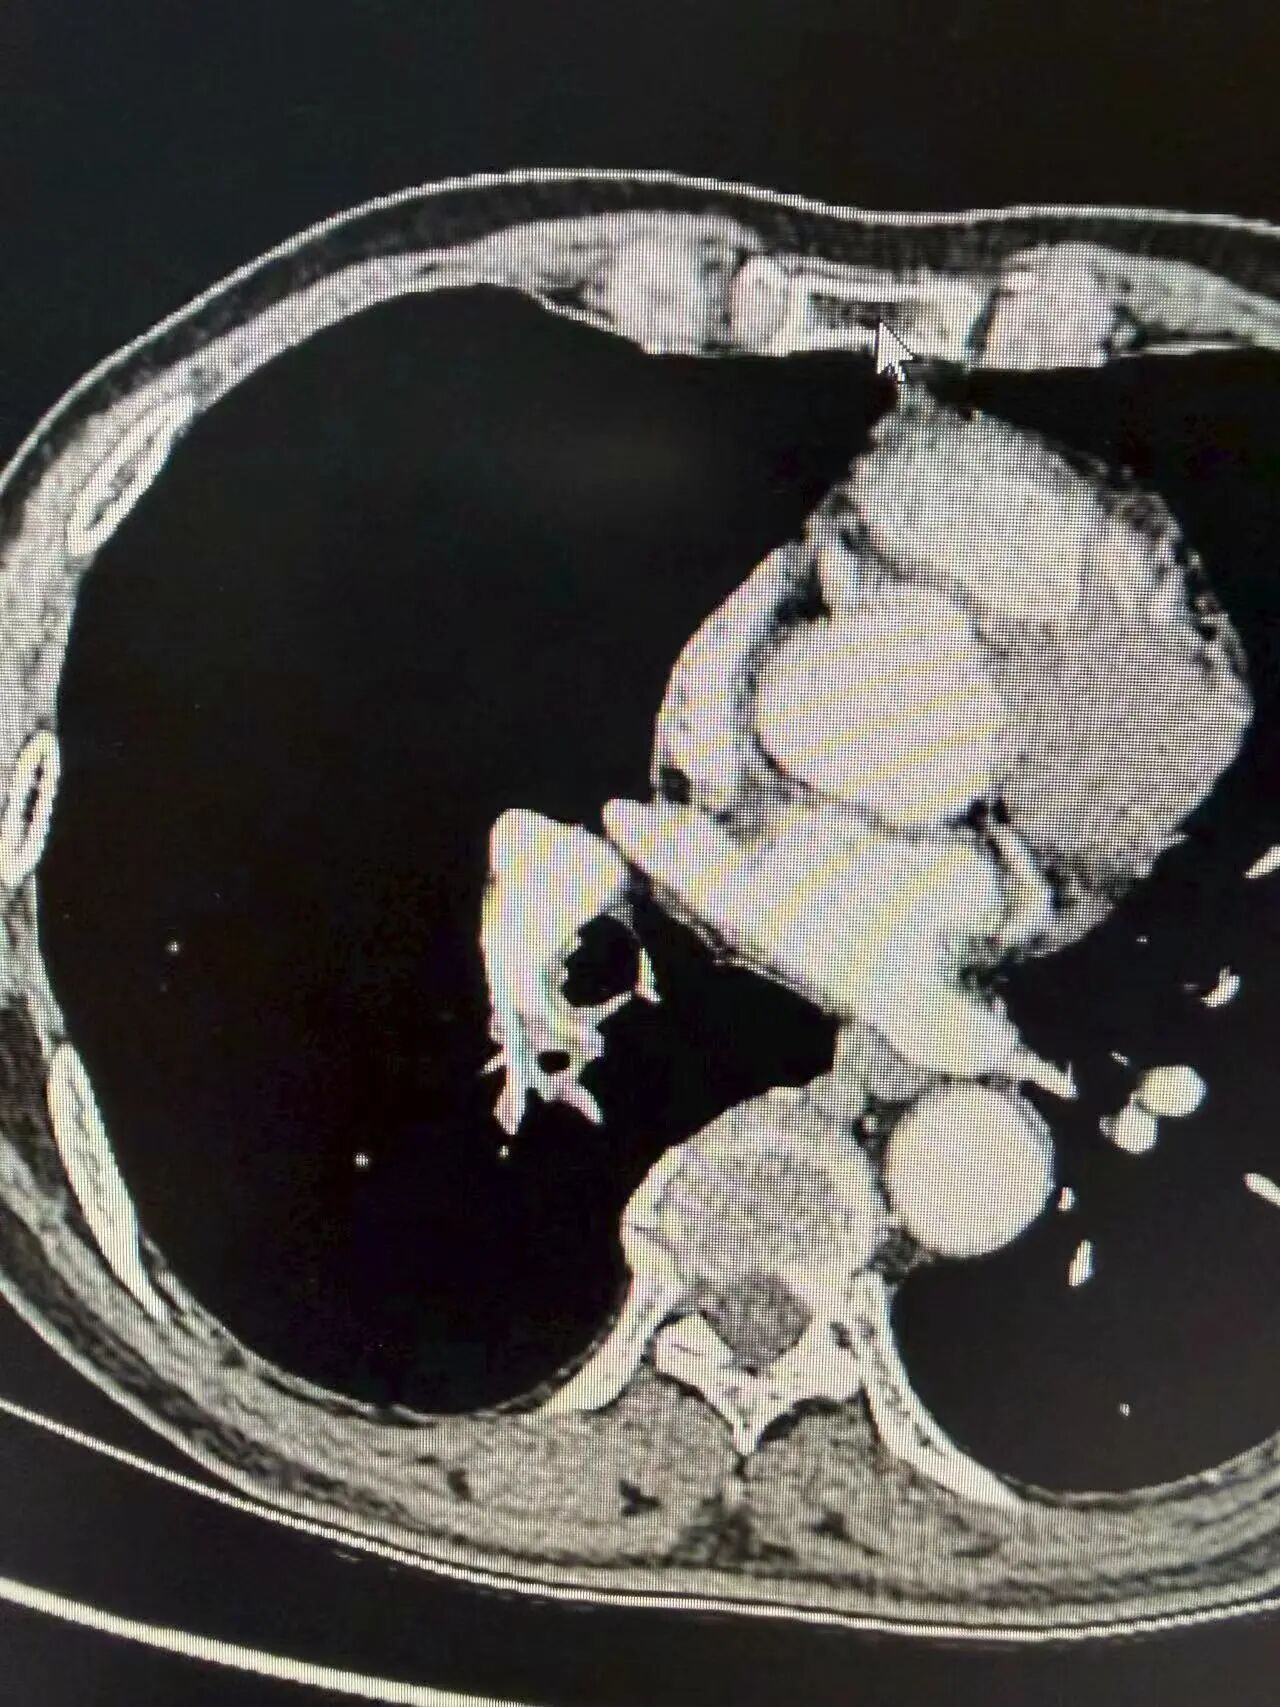

经免疫联合化疗后,胸片上原右肺门占位明显缩小,阴影范围显著减小,肿瘤与周围血管界限变得清晰